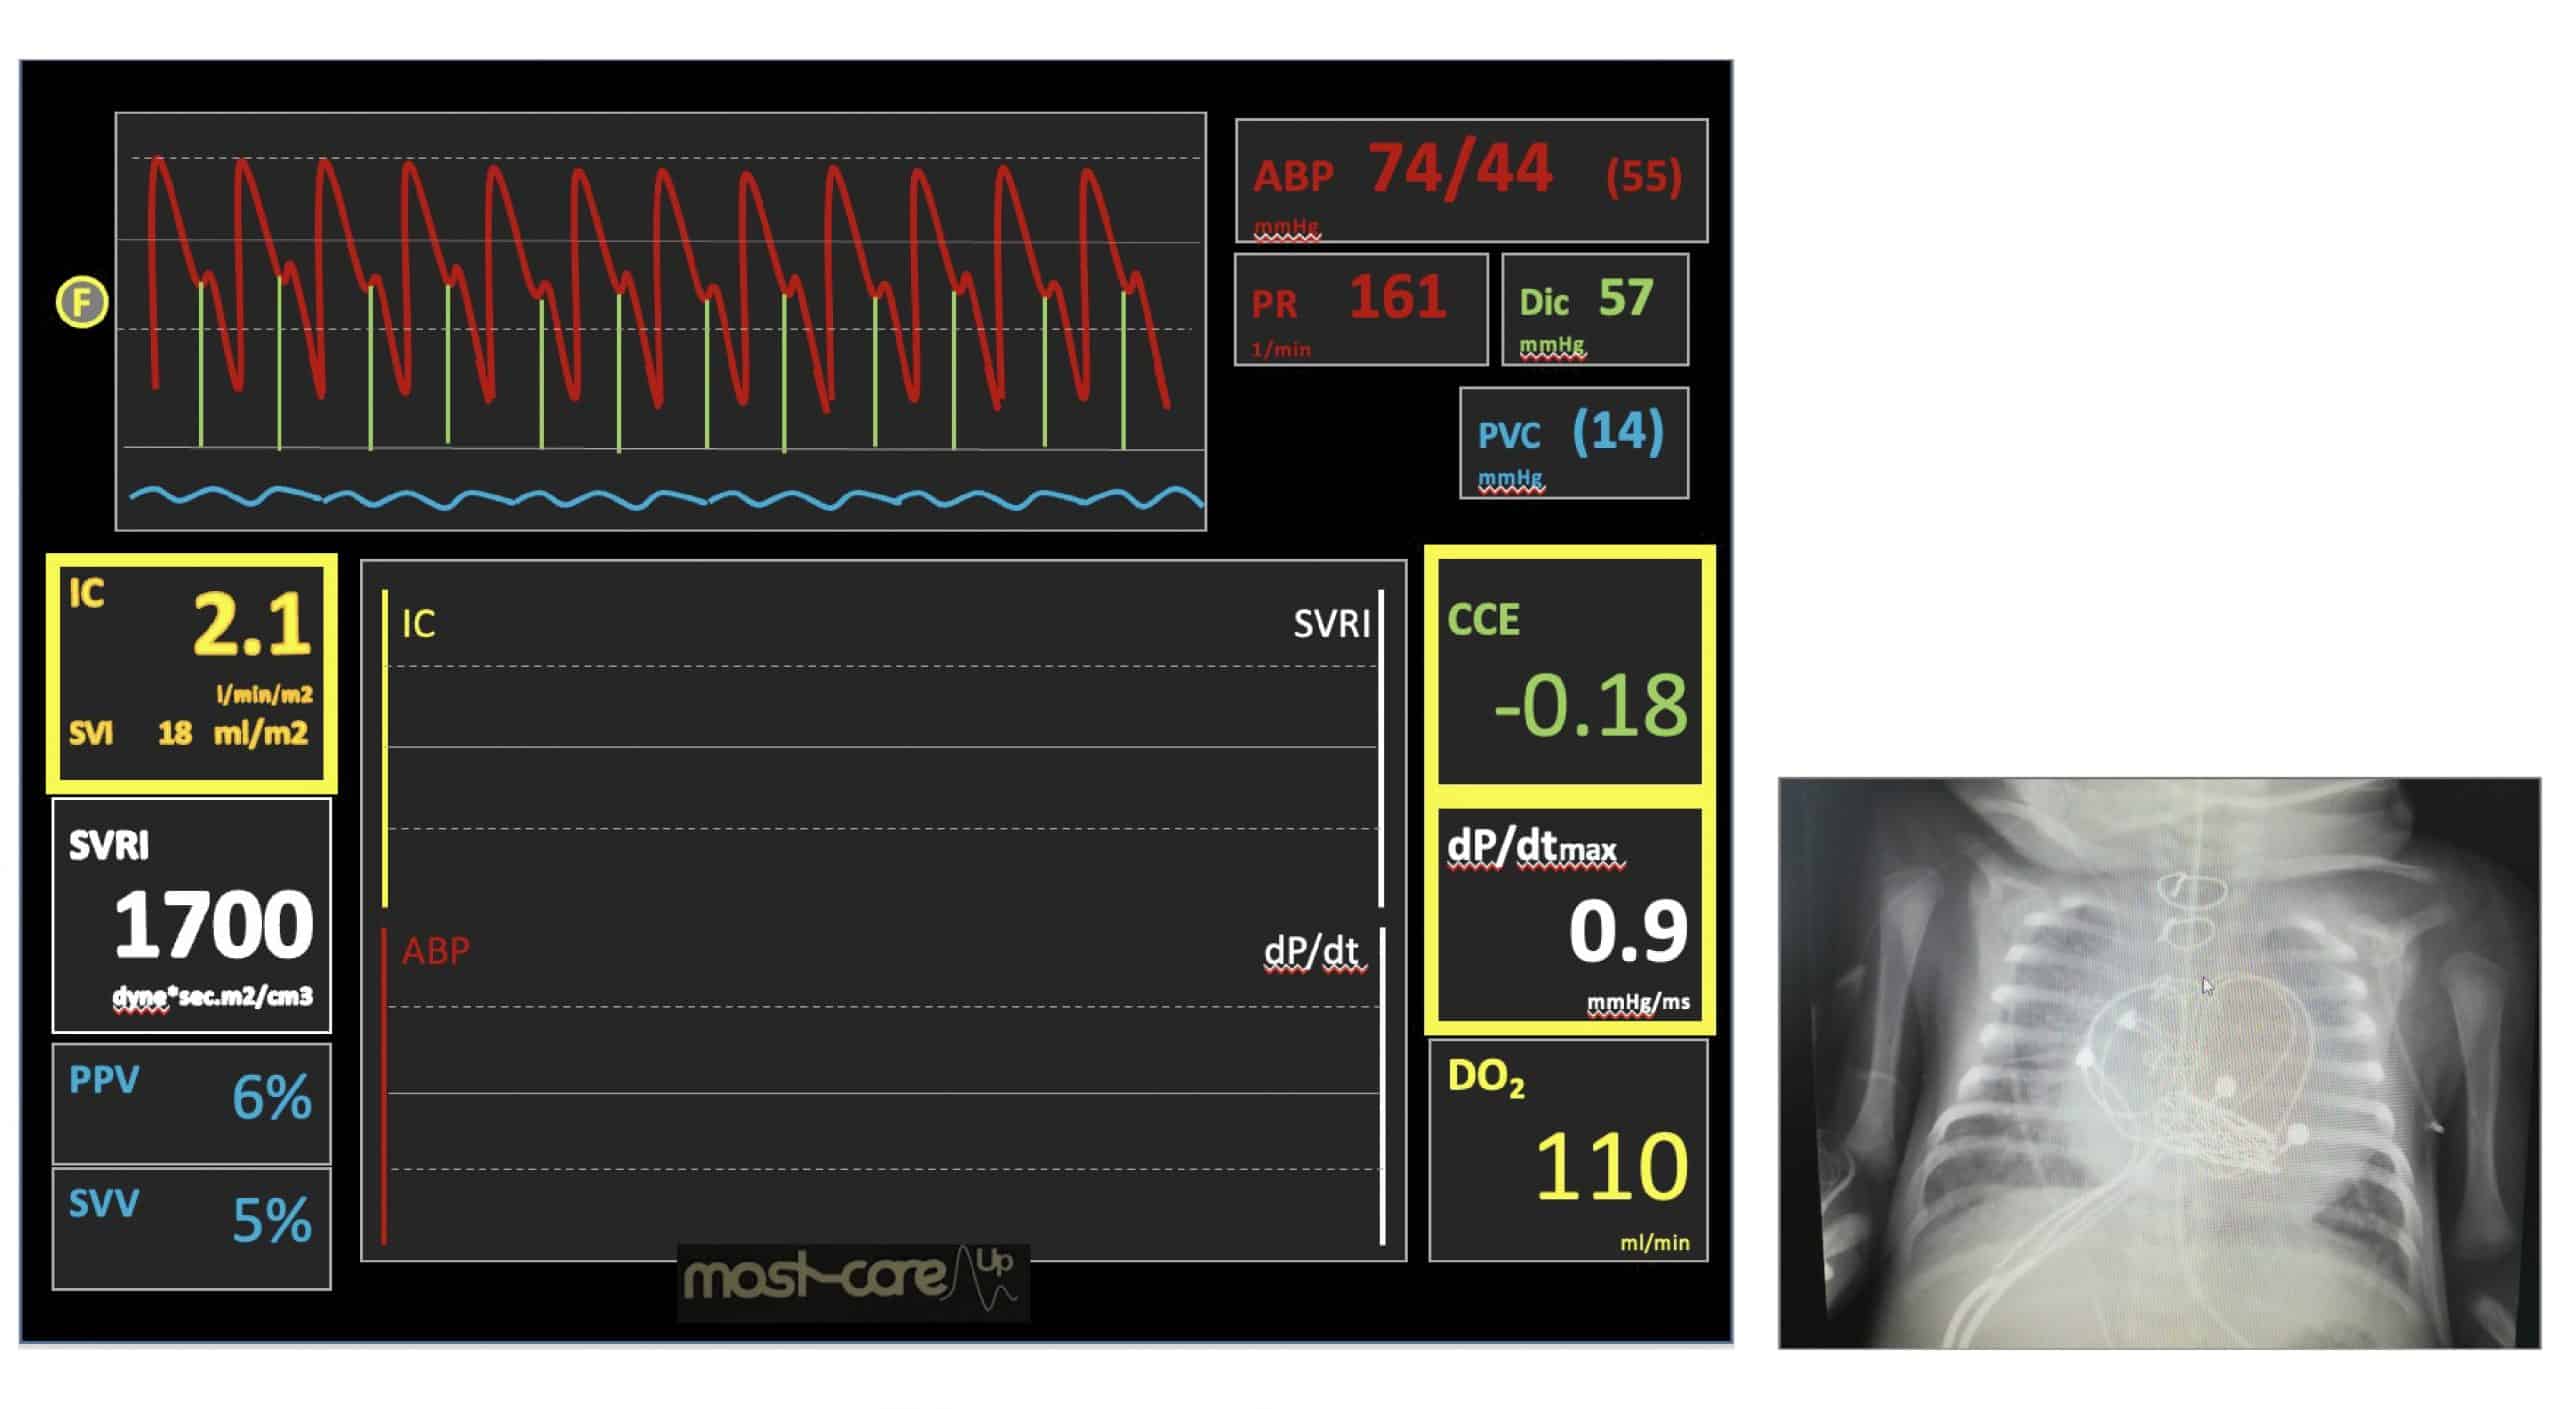

Se trata de un paciente, como se puede visualizar en la imagen, que en el momento de la extubación estaba taquicárdico, con unas tensiones medias adecuadas y polipneico.

Para la monitorización se utilizó el monitor MostCare Up. Este monitor utiliza el método P.R.A.M. para extraer los datos hemodinámicos.

Se trata de un método basado en el análisis del contorno del pulso que no necesita calibración, ya que, para estimar la Z, latido a latido, se basa en métodos físico-matemáticos avanzados. De esta forma, es capaz obtener valores fidedignos y a tiempo real independientemente de las características de cada paciente.

En la pantalla del monitor se observó, como se puede ver en la imagen:

- Índice cardiaco (IC) de 2.1 /min/m2

- Volumen sistólico (SV) de 18 m/m2

- Resistencia vascular sistémica (SVR) de 1.700 dynas·seg3/cm3

- dP/dtmáx. de 0.9 mmHg/ml

- Ciclo de eficiencia cardiaca (CCE) de -0.18

- DO2 de 110 ml/min

Los datos de MostCare Up apoyaban la baja vasoconstricción periférica con unas resistencias periféricas elevadas, irritabilidad continua, no solo por el edema, también por la situación de bajo gasto cardiaco con hipertensión y taquicardia, y una situación, por la congestión pulmonar, de polipnea con tiraje moderado.